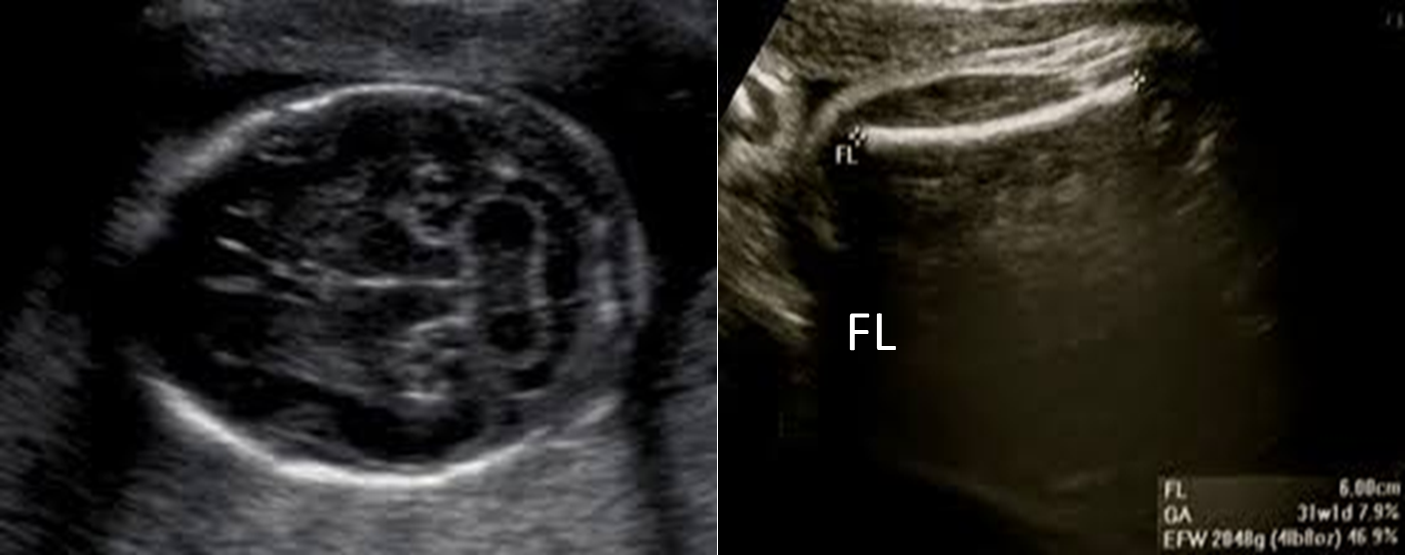

Measuring Sac VS CRL

Measuring gestational age at second & third trimester